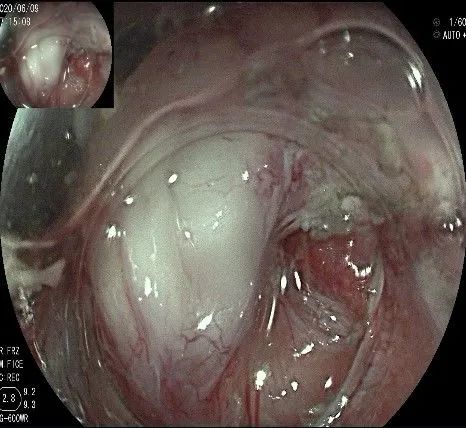

在食管腔内,瘤体的两侧行粘膜下注射后,在瘤体顶部纵向自口侧向肛侧切开食管粘膜。

向下一直切开至齿状线处,白色为鳞状上皮,红色为腺上皮,颗粒样的部分,就是炎性息肉。切开后可见瘤体为白色,表面有血管网,质地较韧。